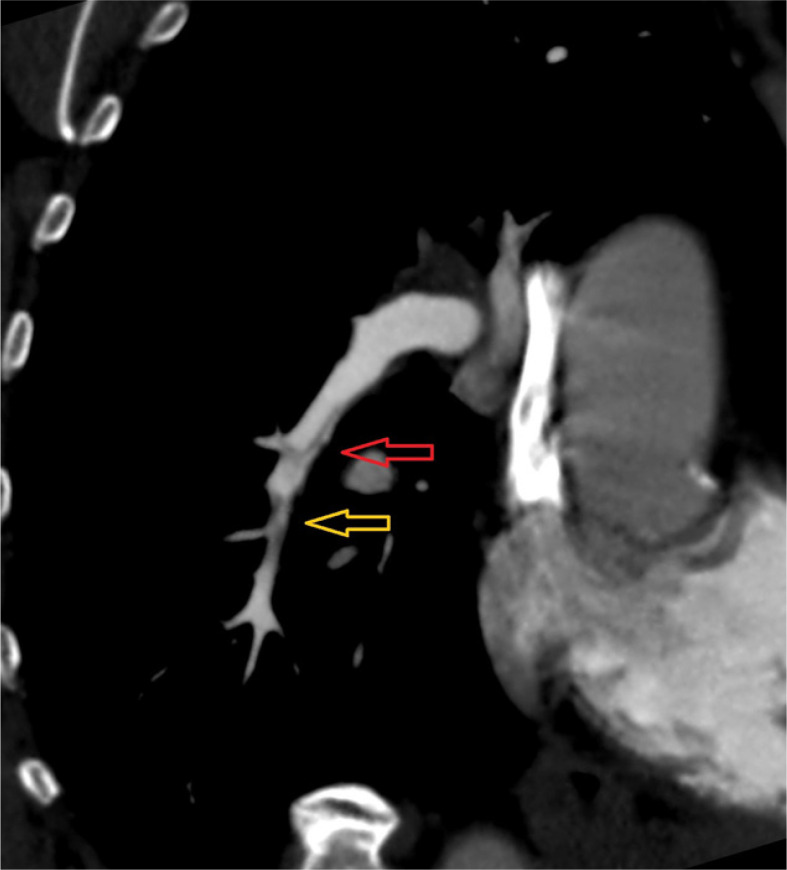

Results: CTEPH patients exhibited vessel narrowing, intimal irregularities, bands, and webs in all cases (100%), with the highest diagnostic value at the segmental level (AUC = 0.906). Mosaic perfusion and variability in vessel size demonstrated moderate predictive value (AUC = 0.740 and AUC = 0.788, respectively).